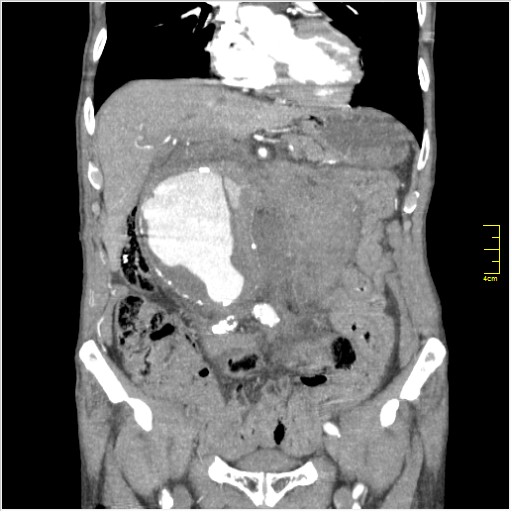

КТ брюшной полости. Мужчина с пальпируемой опухолью в животе

Пациент Т. 64 года, обратился на КТ брюшной полости амбулаторно (!), по направлению семейного врача с диагнозом abdominal mass, буквально: образование брюшной полости.

Huge abdominal aorta aneurism. Simple renal cortical cysts (Bosniak type 1).